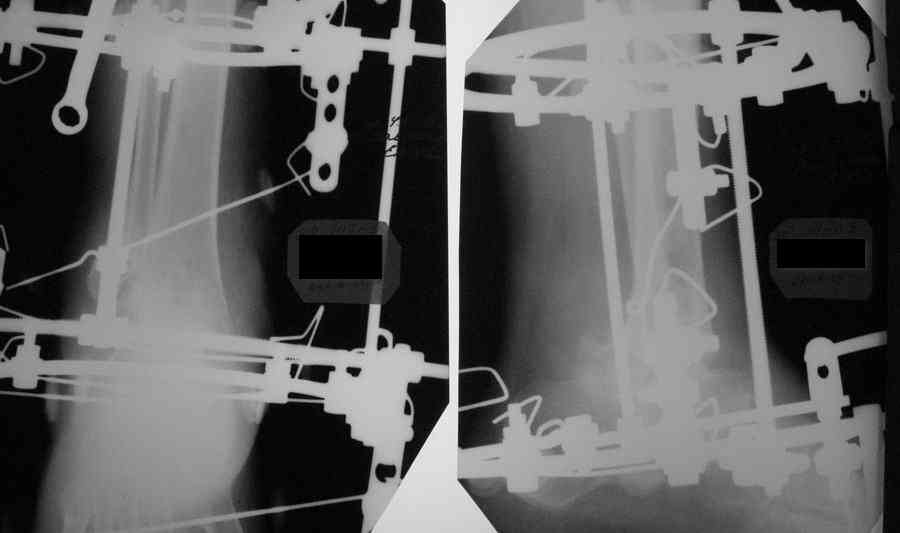

> на снимках (извиняюсь за качество).

Не надо так сильно уменьшать картинку. Размер в пикселах сделать бы побольше по высоте/ширине раза в 2-3, но увеличить степень компрессии.

И файл будет того же размера в килобайтах. Лучше pls фото рентгенограммы переделать.

Стопа сильно смещена кзади, если не ошибаюсь из-за маленького размера снимка.

Александр Николаевич! Постарался переделать рентгенограмму - не знаю лучше ли стало- снимки никудышные:(

Стало разборчивее, хотя компрессию картинки можно было еще увеличить.

Смещение стопы кзади видно более отчетливо. Это намеренно так сделано, поскольку так сформировались контактные поверхности?

И как оценить, насколько эти старания состоятельны? В любом случае, при артродезе голеностопного сустава фиксация пятки

избыточна.

В Campbell`s рекомендуется смещение тарана чуть кзади (чуть- цифры нет), но контакт действительно в таком положении получился максимальным, хотя, я думаю, тоже можно постепенно переместить, если это критично.

You want to have your heel as posterior, especially when the contact is better, but also for good lever (Ri4ag) for the gastroc complex.AL